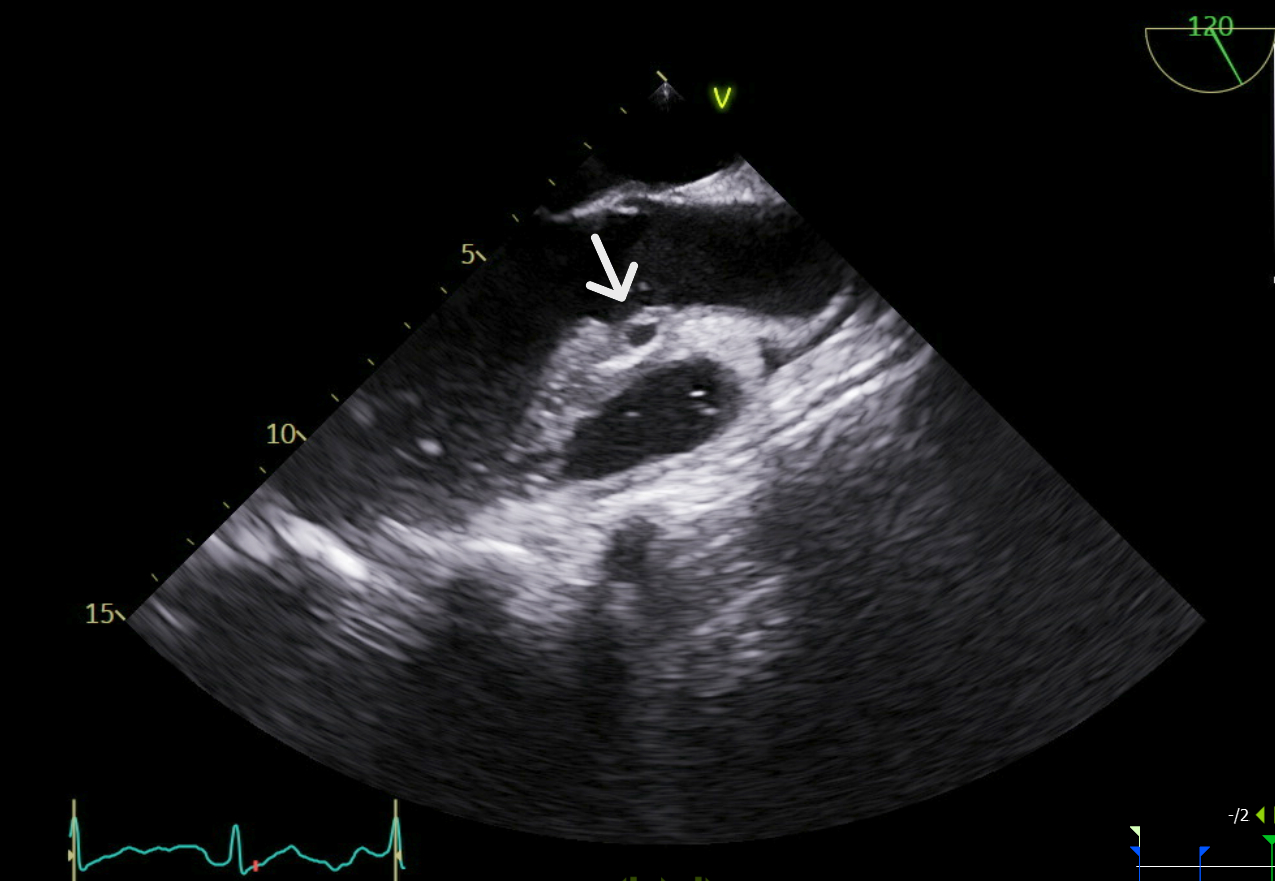

Transthoracic echocardiography (TTE) showed an ejection fraction of 58% with a mobile echodensity on the aortic valve, severe aortic regurgitation, and holo-diastolic flow reversal in the descending aorta. Transesophageal echocardiography (TEE) confirmed a 1.4 × 0.8 cm mobile echogenic mass consistent with vegetation, and an abscess in the right coronary part of the aortic annulus. The patient was started on broad-spectrum antibiotics, including vancomycin and ampicillin-sulbactam.